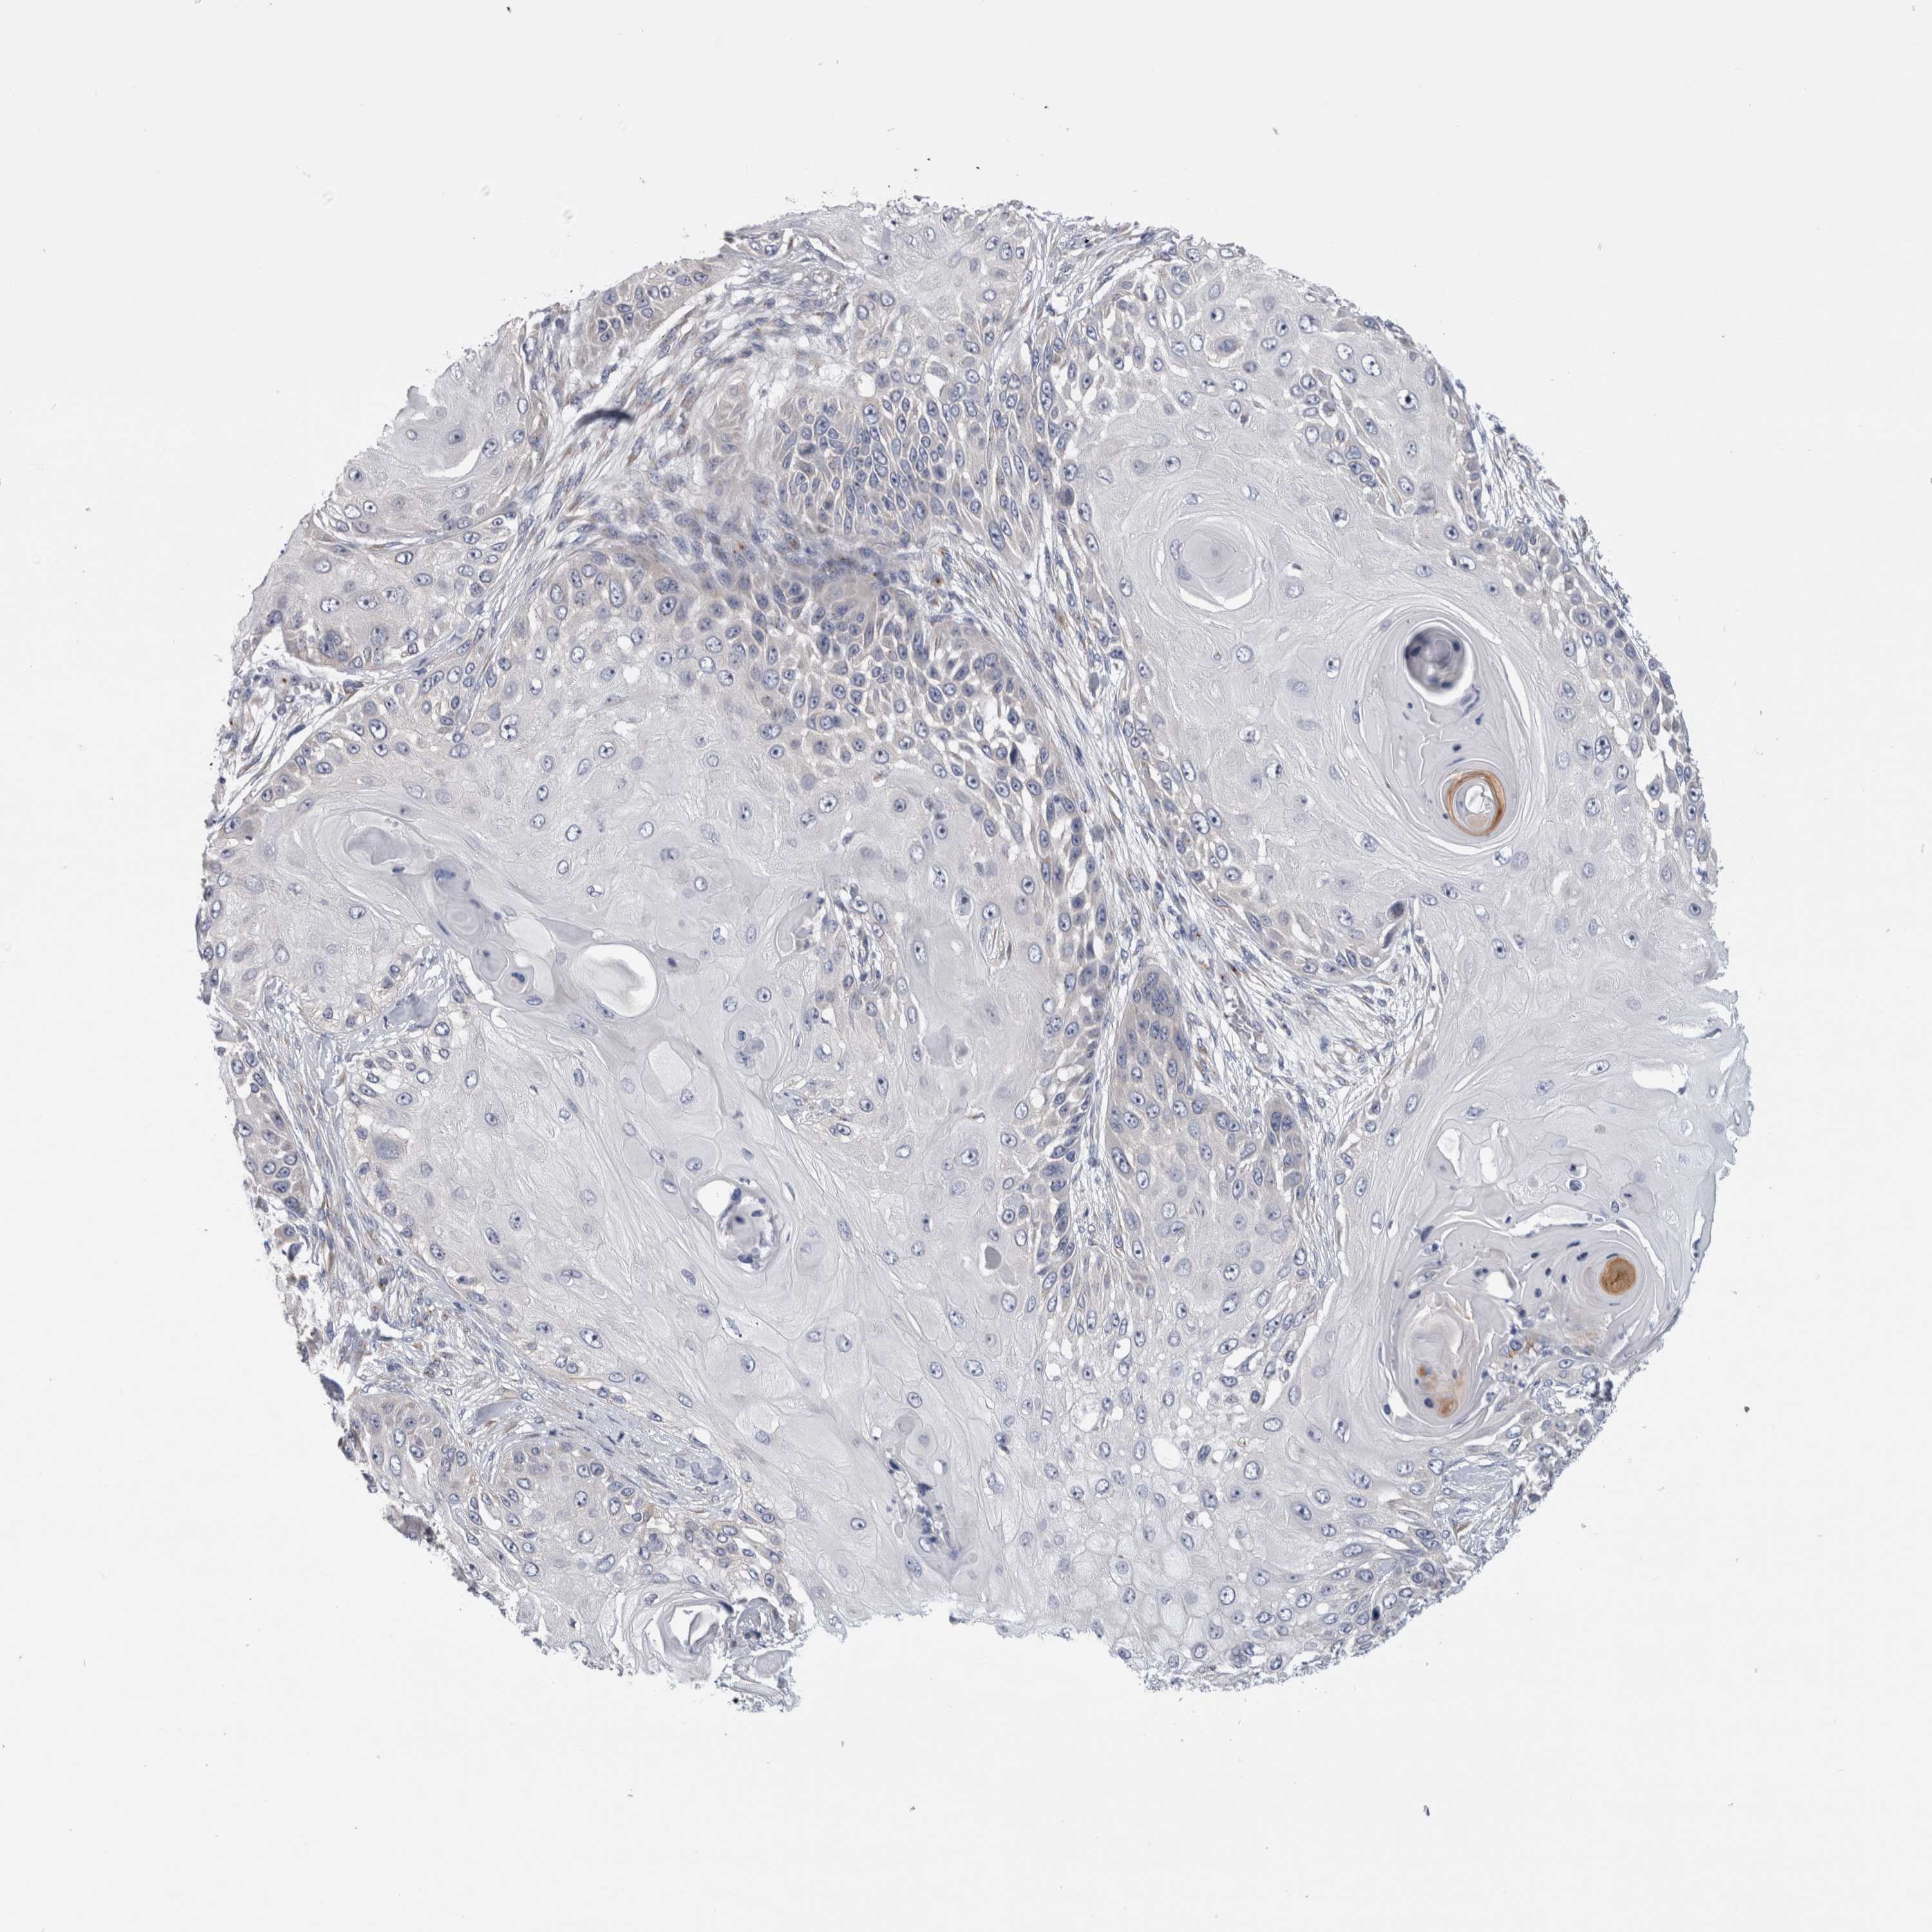

CANCER SKIN CANCER Show tissue menu

SKIN CANCER - Protein expressioni

A mouse-over function shows sample information and annotation data. Click on an image to view it in a full screen mode. Samples can be filtered based on level of antibody staining by selecting one or several of the following categories: high, medium, low and not detected. The assay and annotation is described here.

Each image is clickable and will lead to virtual microscopy that enables deeper exploration of all samples and also displays staining intensity scores, fraction scores and subcellular localization as well as patient and tissue information for each sample.

Antibody HPA008548

Antibody HPA026109

Antibody CAB012909

Squamous cell carcinoma, NOS

Basal cell carcinoma

Squamous cell carcinoma, metastatic, NOS